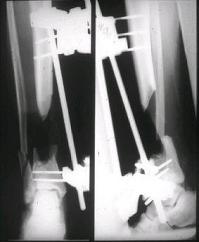

После пары Irrigation& Debridment с вакуумом можно провести окончательную фиксацию интрамедуллярным методом. Чем быстрее, тем лучше, потому что сроки нахождения наружных фиксаторов на конечности тоже имеют значение, риск осложнения увеличивается после длительного пребывания наружного фиксатора.

Открытые переломы, если имеется хороший доступ из раны можно сопоставить и зафиксировать первично пластиной, потому что несопоставленные переломы намного труднее репонируется в поздние сроки. Активизация больного за счет стабилизации кости благоприятно влияет на сращение, а также облегчается манипуляция по закрытию дефекта.

Необходимо доказать проникновение инфекции в кость, иначе агрессивные сегментарные остеотомии кости удлиняет процесс восстановления.

Показания к применению мышечно-ротационной пластики на голени являются обнаженный фрагмент кости, мышца, прикрывая кость восстанавливает питание, а снаружи мышца служит ложем для кожной пластики.

здесь случай с политравмой, перелом зафиксирован наружным фиксатором, после третьей irrigation&debridment фиксация бедра пластиной с последующей кожной пластикой.